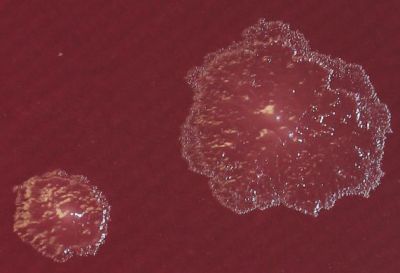

Сред многобройните бактерии и микроби, обитаващи човешкия стомашно-чревен тракт, изследователи идентифицираха вид бактерия, който може самостоятелно да ограничи наддаването на тегло и да подобри метаболитното здраве.

В ново изследване, водено от Университета на Юта, бактерията Turicibacter показа способността да намалява наддаването на тегло при мишки на високомаслена диета. Тя произвежда мастни киселини, които контролират вредните мазнини, наречени церамиди, свързани с метаболитни заболявания като диабет тип 2 и сърдечно-съдови проблеми.

При експерименти с добавки от Turicibacter, мишките, дори на високомаслена диета, показаха по-ниско наддаване на тегло, намалени нива на глюкоза в покой, по-малко телесни мазнини и подобрени липидни профили. Въпреки това, популацията на бактерията се влияе от диетата – твърде много наситени мазнини потискат растежа ѝ, но след премахване на тези мазнини растежът ѝ се възстановява.

Учени подчертават, че Turicibacter е само един от потенциално многото микроби, които могат да бъдат използвани за превенция и лечение на метаболитни заболявания. Добавките с тези бактерии и техните липиди биха могли да бъдат персонализирани според индивидуалния микробиом, което ги прави по-безопасна и целенасочена алтернатива на настоящите лекарства като Оземпик.

„С по-нататъшно изучаване на отделни микроби ще можем да ги превърнем в лекарства и да създадем консорциуми от бактерии, които да компенсират липсите при хора с различни заболявания,“ казва Кендра Клаг, първи автор на изследването.